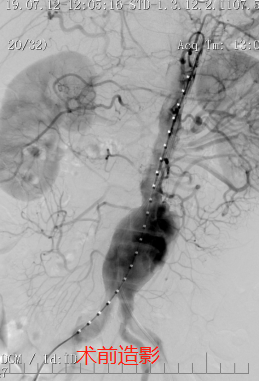

腹主动脉瘤是人体的腹主动脉由于某些原因而扩张并膨胀达到一定程度所引起的一种疾病,虽然是一种良性疾病,但其一旦破裂会引起致命的大出血,是肚子里藏着的一颗随时致命的“炸弹”。安医大一附院血管甲状腺外科主任陈智勇指出:腹主动脉瘤不仅有破裂的风险,且瘤腔内血液流动呈湍流,容易形成附壁血栓,导致远端动脉栓塞。直径超过5cm,或是有腹腔脏器压迫症状或者远端动脉栓塞,或是有腹痛症状濒临破裂,或者增长较快的腹主动脉瘤就需要治疗了。

手术方式包括两类:一是“巨创”,就是传统的开刀手术方法,但这种手术创伤巨大,大部分患者术后需要进入重症监护病房过渡。如果病人一般的情况比较好,对手术的耐受度比较高,采取这种方法是一个很好的治疗手段。二是“微创”,还有一种方法就是近年来发展迅速的微创技术-腹主动脉瘤腔内修复术(Endovascular Aortic aneurysm Repair, EVAR),就是把一个带膜的大支架放在主动脉里边,使得血液通过这个支架内流动,这种治疗方式不但具有和开腹手术一样的效果,而且创伤小、恢复快。目前我院血管甲状腺外科已经常规开展以上两项技术。

随着技术和材料的进步,我院血管甲状腺外科在“微创”的基础上,逐渐推广了“无创”的腹主动脉瘤腔内隔绝术,也就是经皮股动脉穿刺入路的腹主动脉瘤腔内修复术(Percutaneous Endovascular Aortic aneurysmRepair, PEVAR),没有切口,只有两个小小的穿刺点,其创伤更小,病人恢复更快。同时,还对解剖条件合适但合并症较多的患者,成功实行了局麻下P-EVAR术,最大程度降低了麻醉风险。目前我院血管甲状腺外科已成功完成近10例腹主动脉瘤的穿刺微创腔内修复手术,无一例并发症,患者术后恢复很快,手术当日就能恢复饮食,术后第一日就可以下床活动,很快就可以康复出院,以最小的创伤方式解决了最危险的主动脉疾病,该技术达到省内领先,国内先进水平。